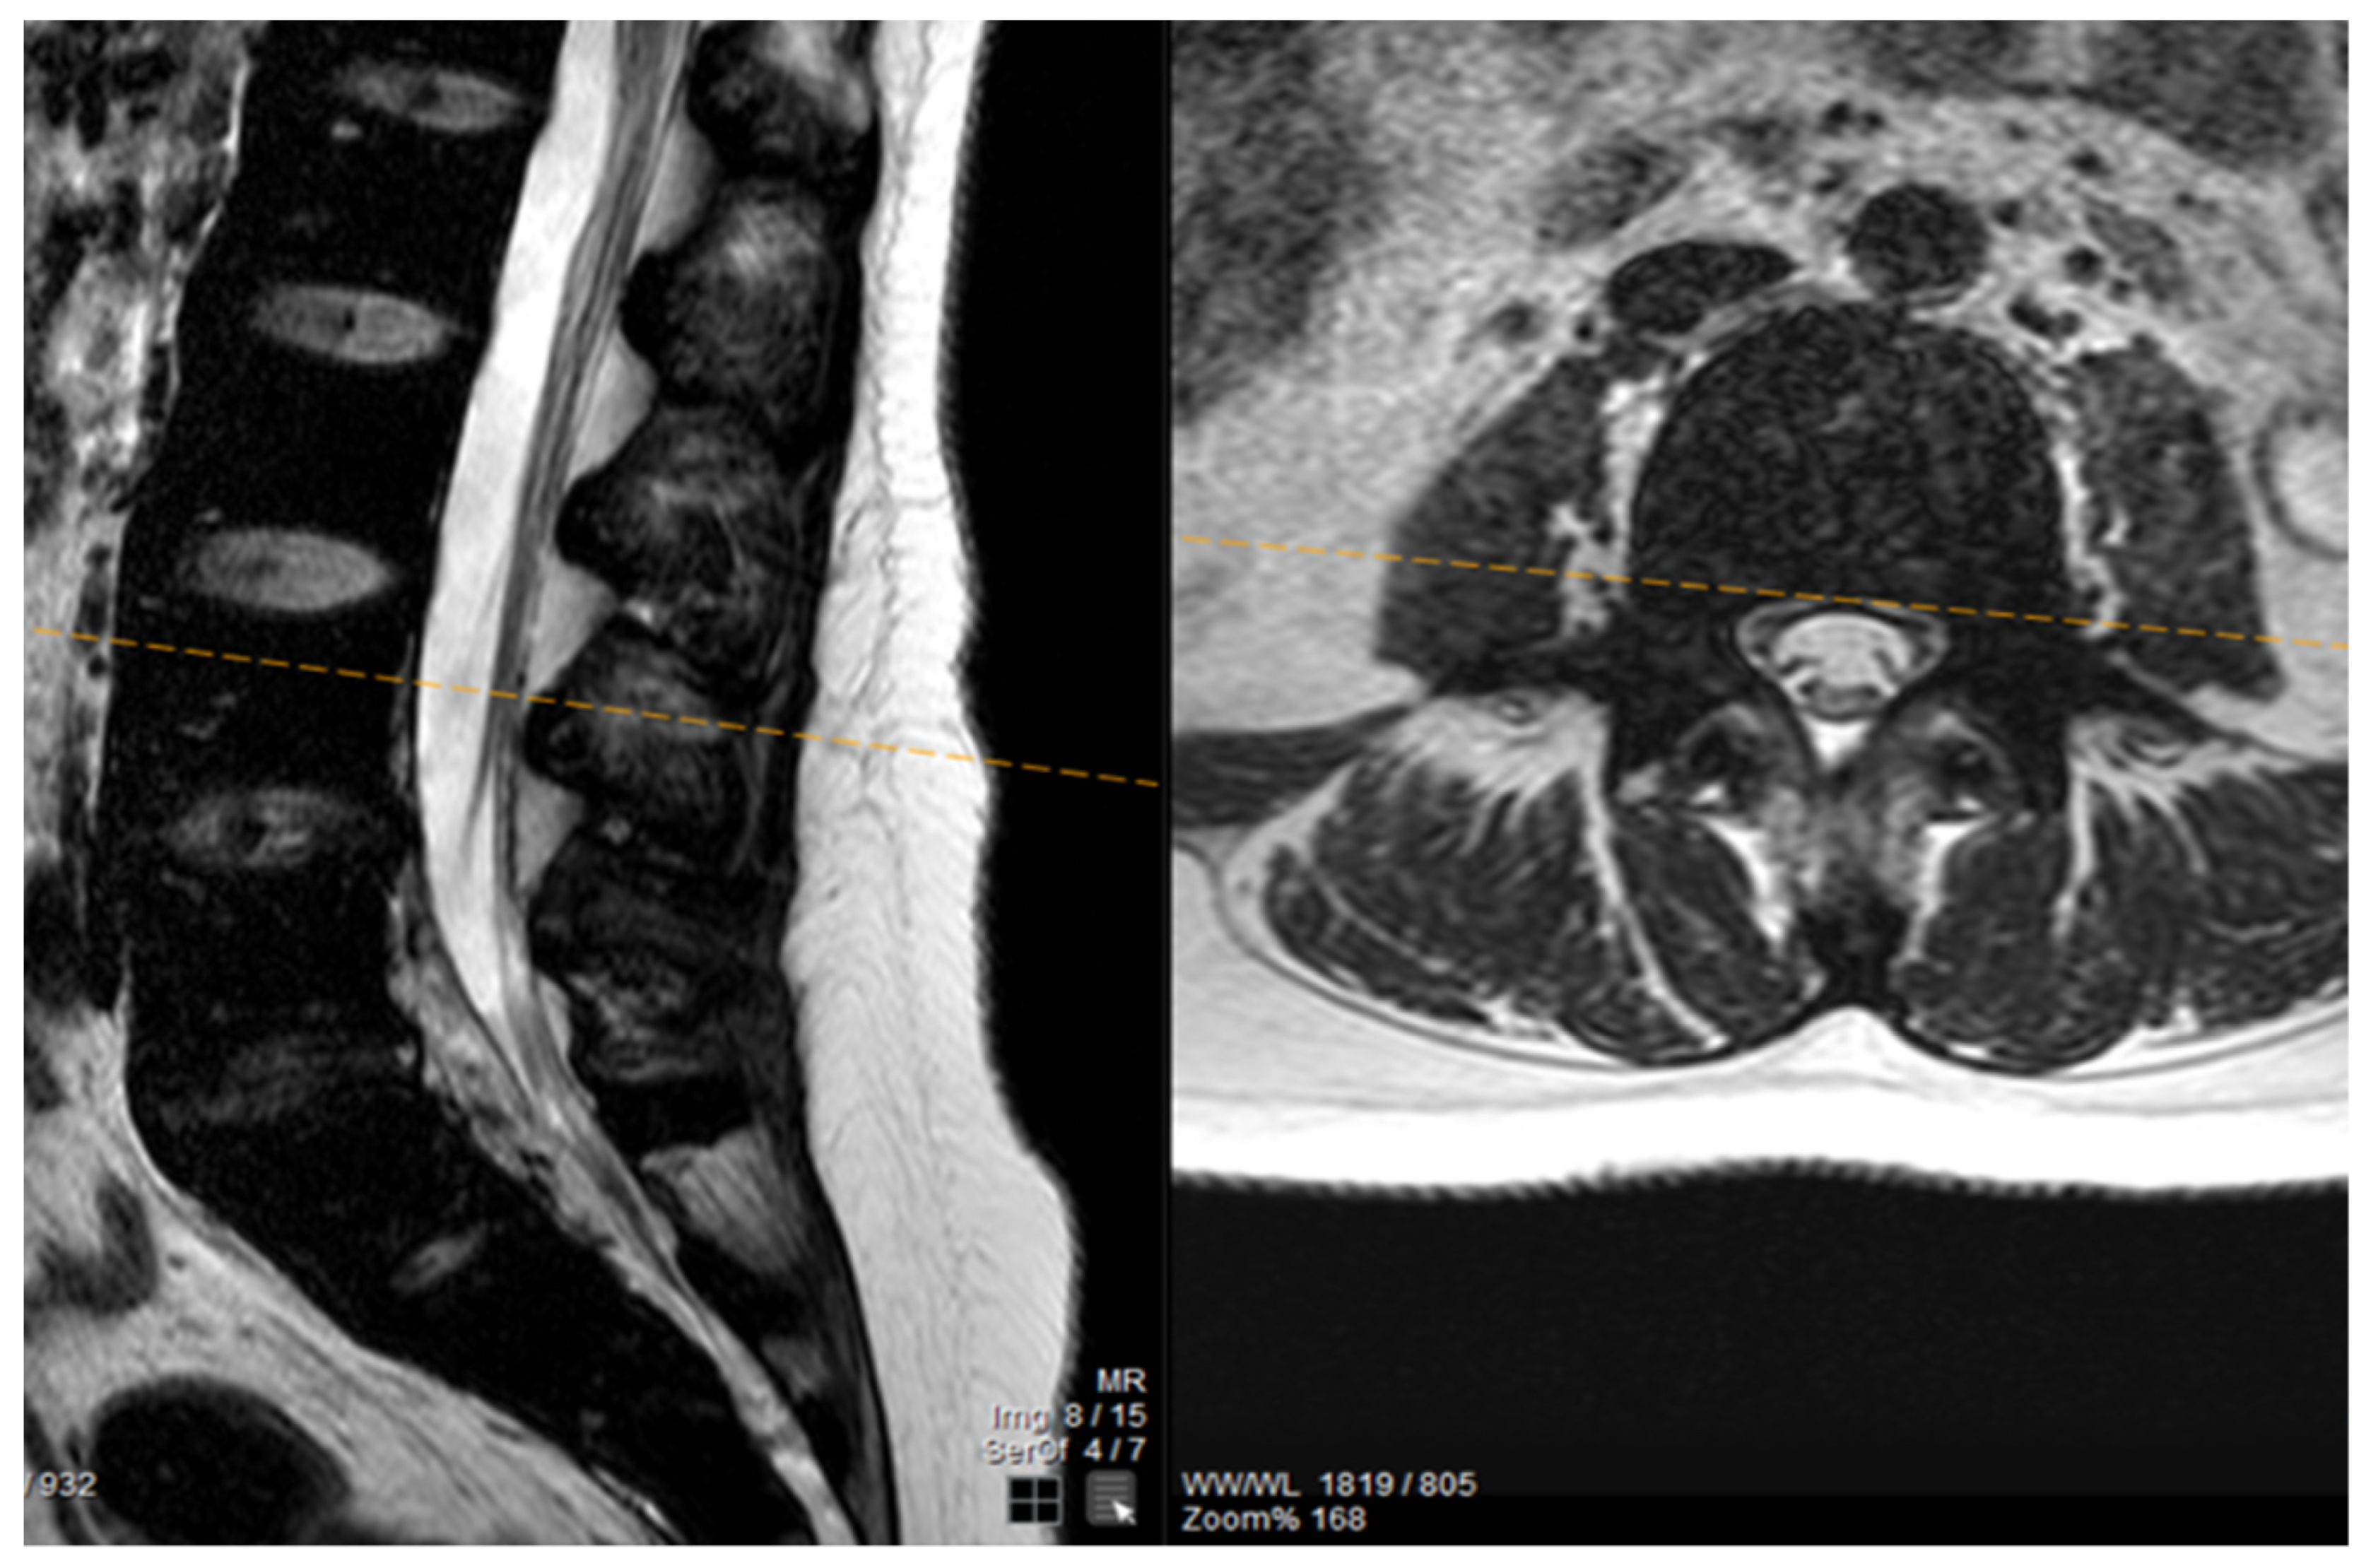

The patient noted a gradual improvement in neurological manifestations related to mobility and sensitivity. Upon discharge, she continued self-catheterization due to incomplete restoration of urination. Subsequently, the patient maintained subcutaneous iron chelation treatment with deferoxamine at a dosage of 80 mg/kg. Severe aplasia occurred two months after initiating hydroxyurea, leading to the discontinuation of both deferiprone and hydroxyurea until complete hematological recovery. Despite efforts to reintroduce hydroxyurea, the patient experienced aplasia again, prompting the decision to permanently cease this medication. Six months after the initial symptom onset, MRI findings indicated a reduction in mass and iron deposition (Figure 3 and Figure 4). The patient continued intensive iron chelation therapy with a combination of deferiprone and deferoxamine, resulting in a decreased iron load. Transfusions were maintained every 15 days with the goal of achieving hemoglobin levels above 10 g/dL. The patient achieved complete neurological recovery in the sensory and motor aspects, with only a minor improvement noted in neurogenic bladder dysfunction. Despite our patient experiencing severe myocardial iron overload, she maintained satisfactory systolic function in both the left and right ventricles. There were no observed valvular or conduction abnormalities, and the volume overload resulting from hypertransfusion did not adversely affect her overall cardiac function.

Figure 3.

The MRI findings six months after the first appearance of symptoms showed a decrease in mass and iron deposition.